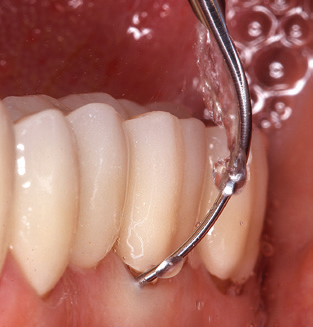

Good illumination of the working field facilitates the process considerably. The system used by the authors achieves this thanks to a 5x LED ring integrated in the handpiece. Naturally, a range of working tips for different indications is also offered. A straight, universally employable tip is the basic instrument required for machine cleaning of natural teeth (Fig. 5a and b). Curved tips, which allow access to exposed furcations, are also available for hard-to-reach areas in the posterior region (Fig. 6).

Of course, working tips for the cleaning of implant surfaces are also indispensable for SPT in patients fitted with implants. The implant cleaning attachment on the system used here is characterised by its tapered, hexagonal design. This design allows light, atraumatic penetration of the peri-implant pocket and displays a good cleaning performance (Fig. 7).

Fig. 4: Flexible probes with millimetre markings are recommended for the probing of dental implants (e.g. Colorvue Kit PCV11KIT6, Hu­Friedy). – Fig. 5a and b: A straight working tip (1P, W&H Dentalwerk Bürmoos GmbH) is a suitable instrument for use on all natural teeth. – Fig. 6: Curved working tips (3Pr/3Pl, W&H Dentalwerk Bürmoos GmbH) lend themselves to the processing of difficult-to-reach areas of the tooth and root surfaces (e.g. furcations). – Fig. 7: The tapered, hexagonal implant cleaning tip (1I, W&H Dentalwerk Bürmoos GmbH) permits atraumatic and efficient cleaning of the crown and abutment surfaces. – Fig. 8: Titanium and carbon curettes are suitable instruments for the manual cleaning of the implant surfaces.